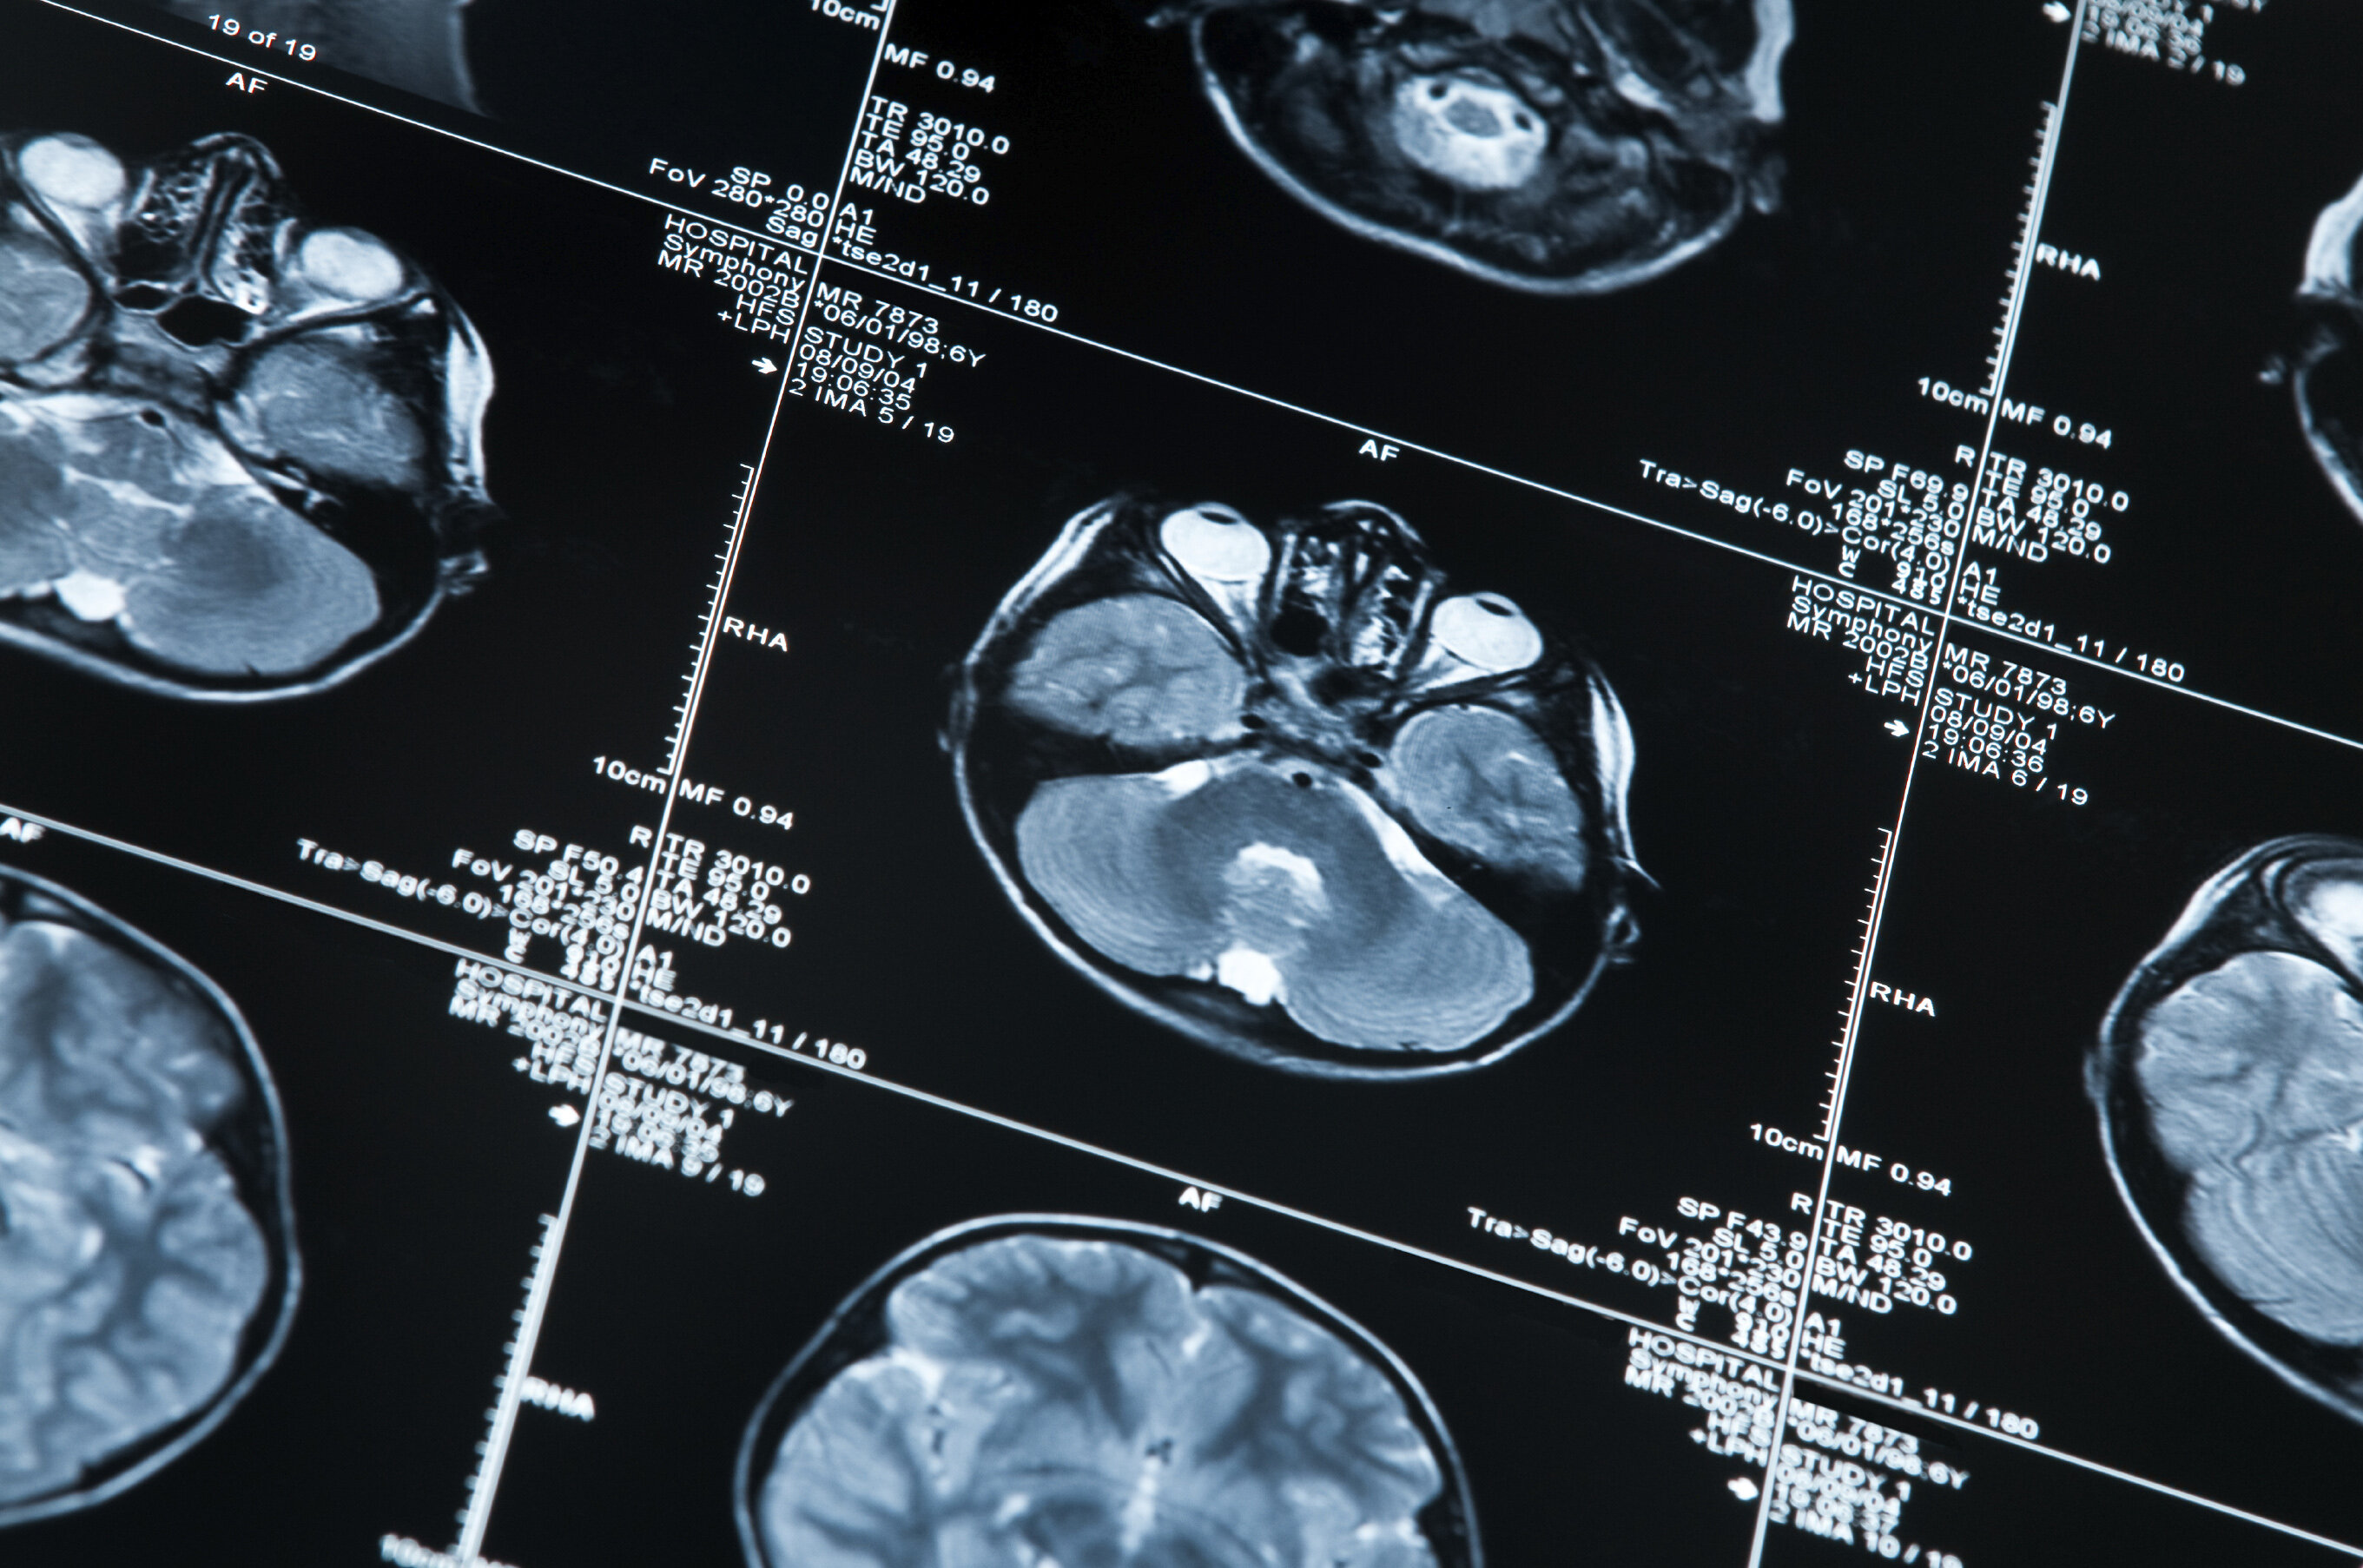

Achievements for EMPIR project researching neurogenerative diseases

MRI scan of a human head

EMPIR project developing non-invasive techniques for diseases such as Alzheimer’s and Parkinson’s has a number of successful outcomes

Recently completed EMPIR project Innovative measurements for improved diagnosis and management of neurodegenerative diseases (15HLT04, NeuroMET) developed reference measurement procedures to accelerate the uptake of minimal invasive methods for the early diagnosis and monitoring of the progression of neurodegenerative diseases such as Alzheimer’s and Parkinson’s. The research explored innovative techniques for early diagnosis and monitoring, based on non-invasive blood and saliva tests, in-vivo magnetic resonance approaches and cognitive assessments.